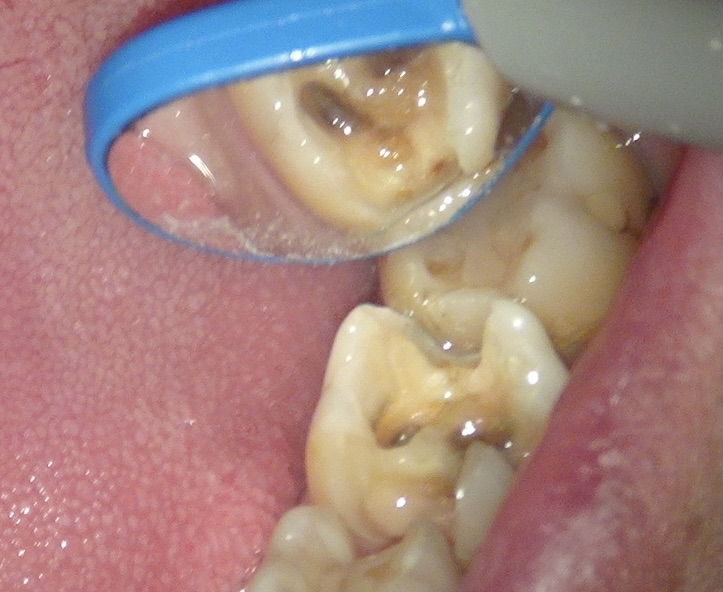

むし歯を取り除いていくと こんな感じになっていました。

取り終わったところで、ラバーダム。

ラバーかけているところと、レジンを詰めたところ。